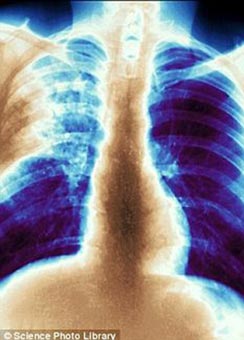

Chẩn đoán bệnh lao trong vòng vài phút